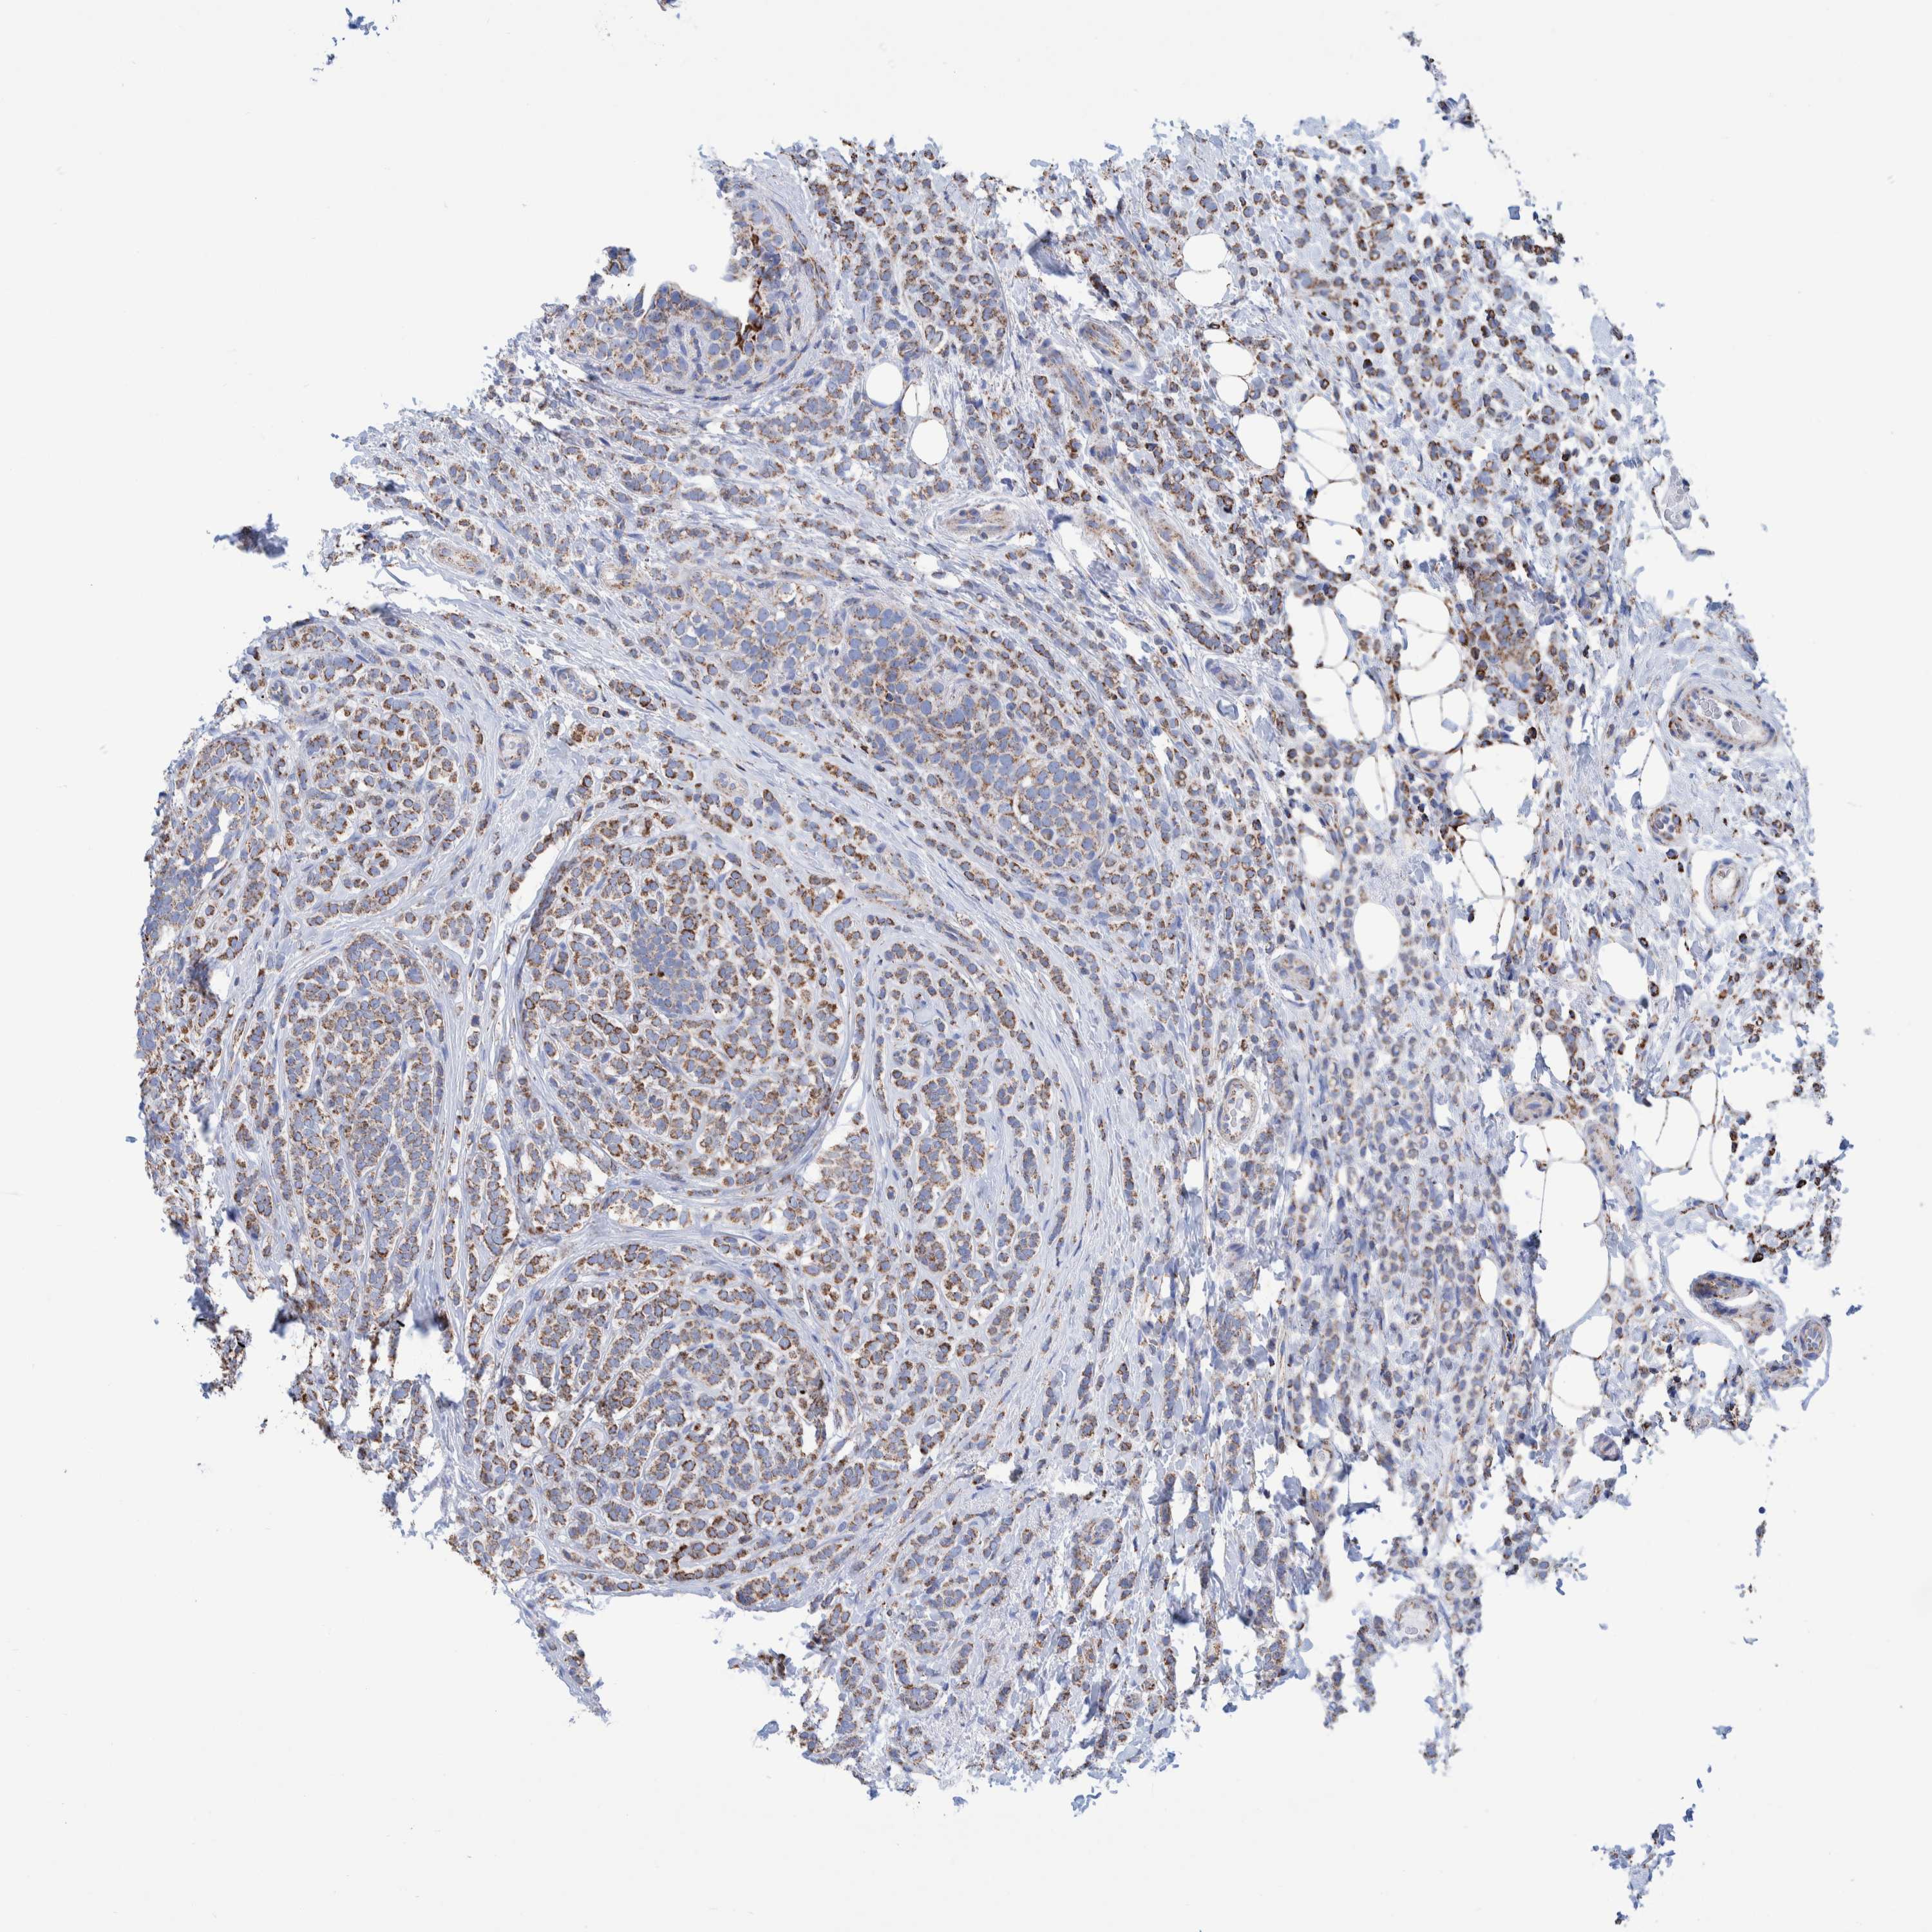

CANCER BREAST CANCER Show tissue menu

Breast cancer

Human cancer